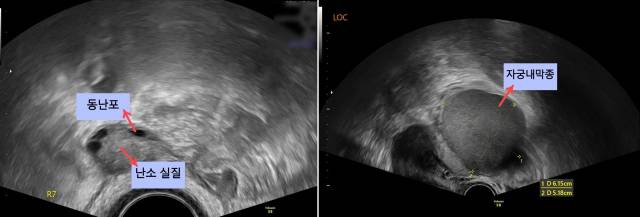

이해를 돕기 위해 환자 사례를 들어보자. 청소년기부터 심한 월경통을 앓았던 A씨는 20대 후반경 자궁경부암 검사를 위해 산부인과에 처음 내원했다가 골반 초음파로 양쪽 난소에서 약 5cm 크기의 난소 낭종을 확인했다. 이후 월경통이 점점 극심해져 난소 낭종 제거술을 받았다. 수술 후 조직검사를 통해 통증의 원인이 자궁내막종임을 확인했고 자궁과 나팔관에서 심한 유착이 관찰됐다. 수술 시 자궁 및 난소에서 유착이 관찰되는 것은 자궁내막증의 또다른 특징이기도 하다. 자궁내막종을 수술적으로 제거하면 난소 기능이 떨어져 가임력이 저하될 수 있다. 실제 A씨는 수술 후 검사 결과 난소 기능(AMH) 수치가 1.1로 크게 떨어져 가임력 보존을 위한 난자 동결 시술을 시행 중이다. 자궁내막증이 더 악화되지 않도록 증상이 있을 때 적절한 치료를 받는 것이 중요하다는 점을 시사한다.